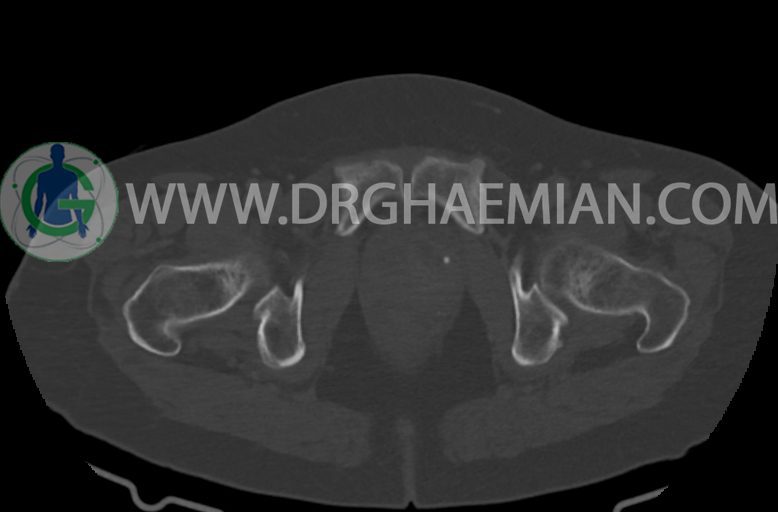

–ساختار Cystic multiseptate همراه با Enhancing thick septation به ابعاد 79x62mm در

لگن دیده می شود که در درجه اول مطرح کننده ی ضایعات نئوپلاستیک تخمدانی نظیر mucinous cyst adenocarcinoma است.

–شواهد هیسترکتومی